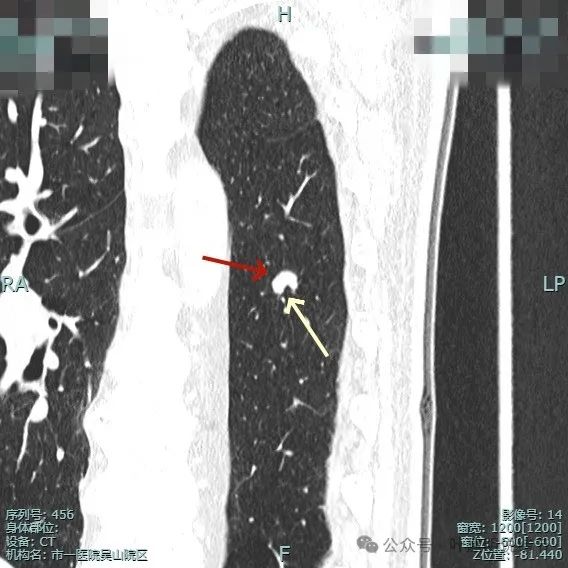

左下背段病灶实性,密度较高,紫色箭头处表面有细锯齿状,桔色箭头示有血管发出分支进入病灶且进入的血管到了结节边上有增粗。

多支血管进入,病灶有膨胀感。

边缘毛糙,细毛刺或锯齿状明显。

整体膨胀性较明显,有少许磨玻璃成分,周围肺野较清晰,血管与之关系密切。